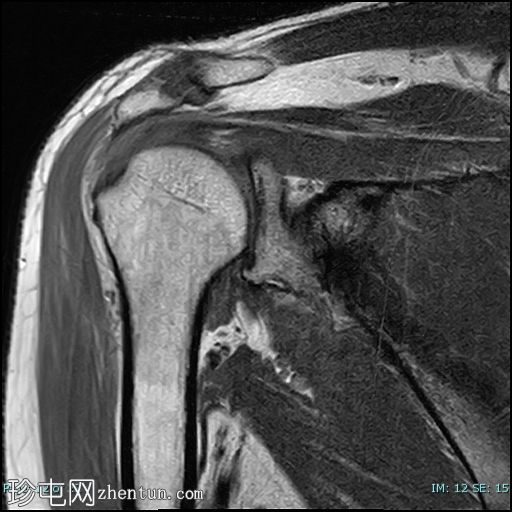

轴位PD

脂肪抑制

冈上肌腱前部纤维及肌腱止点-关键区交界处全层撕裂。撕裂间隙被T2/PD高信号液体填充。肌腱回缩2.1厘米,位于肩峰水平。

未见肱骨头骨内囊性改变或冈上肌腱神经节/黏液囊肿。

冈上肌腱变薄并伴有肌腱病,冈上肌脂肪变性为2级(Goutallier分级)。

本病例展示了退行性冈上肌腱撕裂的典型位置,即肌腱足印和关键区交界处。这与创伤性撕裂(通常发生在肌腱交界处)形成对比。

应注意,不应过度依赖质子密度加权成像序列来诊断肩袖撕裂,因为该序列容易出现魔角伪影,从而模拟撕裂。较长的回波时间序列(例如T2加权成像)可以有效避免这种假阳性结果。